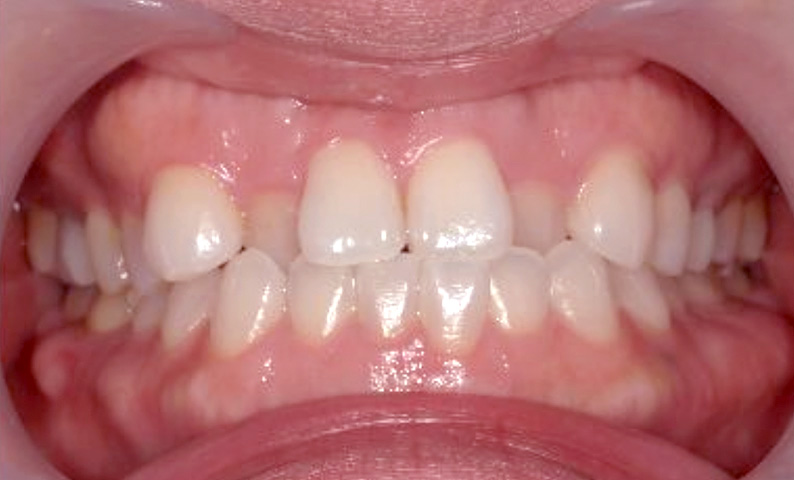

症例_022 上下顎の部分矯正

治療期間:9ヶ月金額:51万円+税女性前歯のガタガタ八重歯

| Before | After |